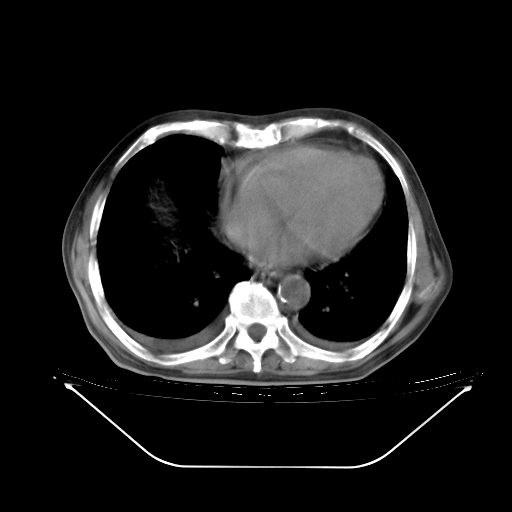

今天复查肺部CT,发现双肺广泛磨玻璃样改变。所以我把3月19日和5月9日相隔50天的肺部CT上传。请大家会诊。

5月9日肺部CT(在4月27日齐鲁医院肺部CT描述部分肺组织磨玻璃样改变,12天后肺组织广泛磨玻璃样改变)

大致读了系列胸部CT:纵隔窗无明显异常,肺窗:从4、27至今:主要是双肺中下野外带可见毛玻璃样改变,目前处于急性肺泡炎阶段,至于原因考虑1、结替组织或胶原血管性疾病所致?2、恶性疾病如恶组在肺部所致的表现或细支气管肺泡癌?3、药物或其它原因如肺蛋白沉着症所致肺泡炎目前不太可能?总之,明天就去请我院的呼吸科、感染科、血液科和临免专家会诊哈。